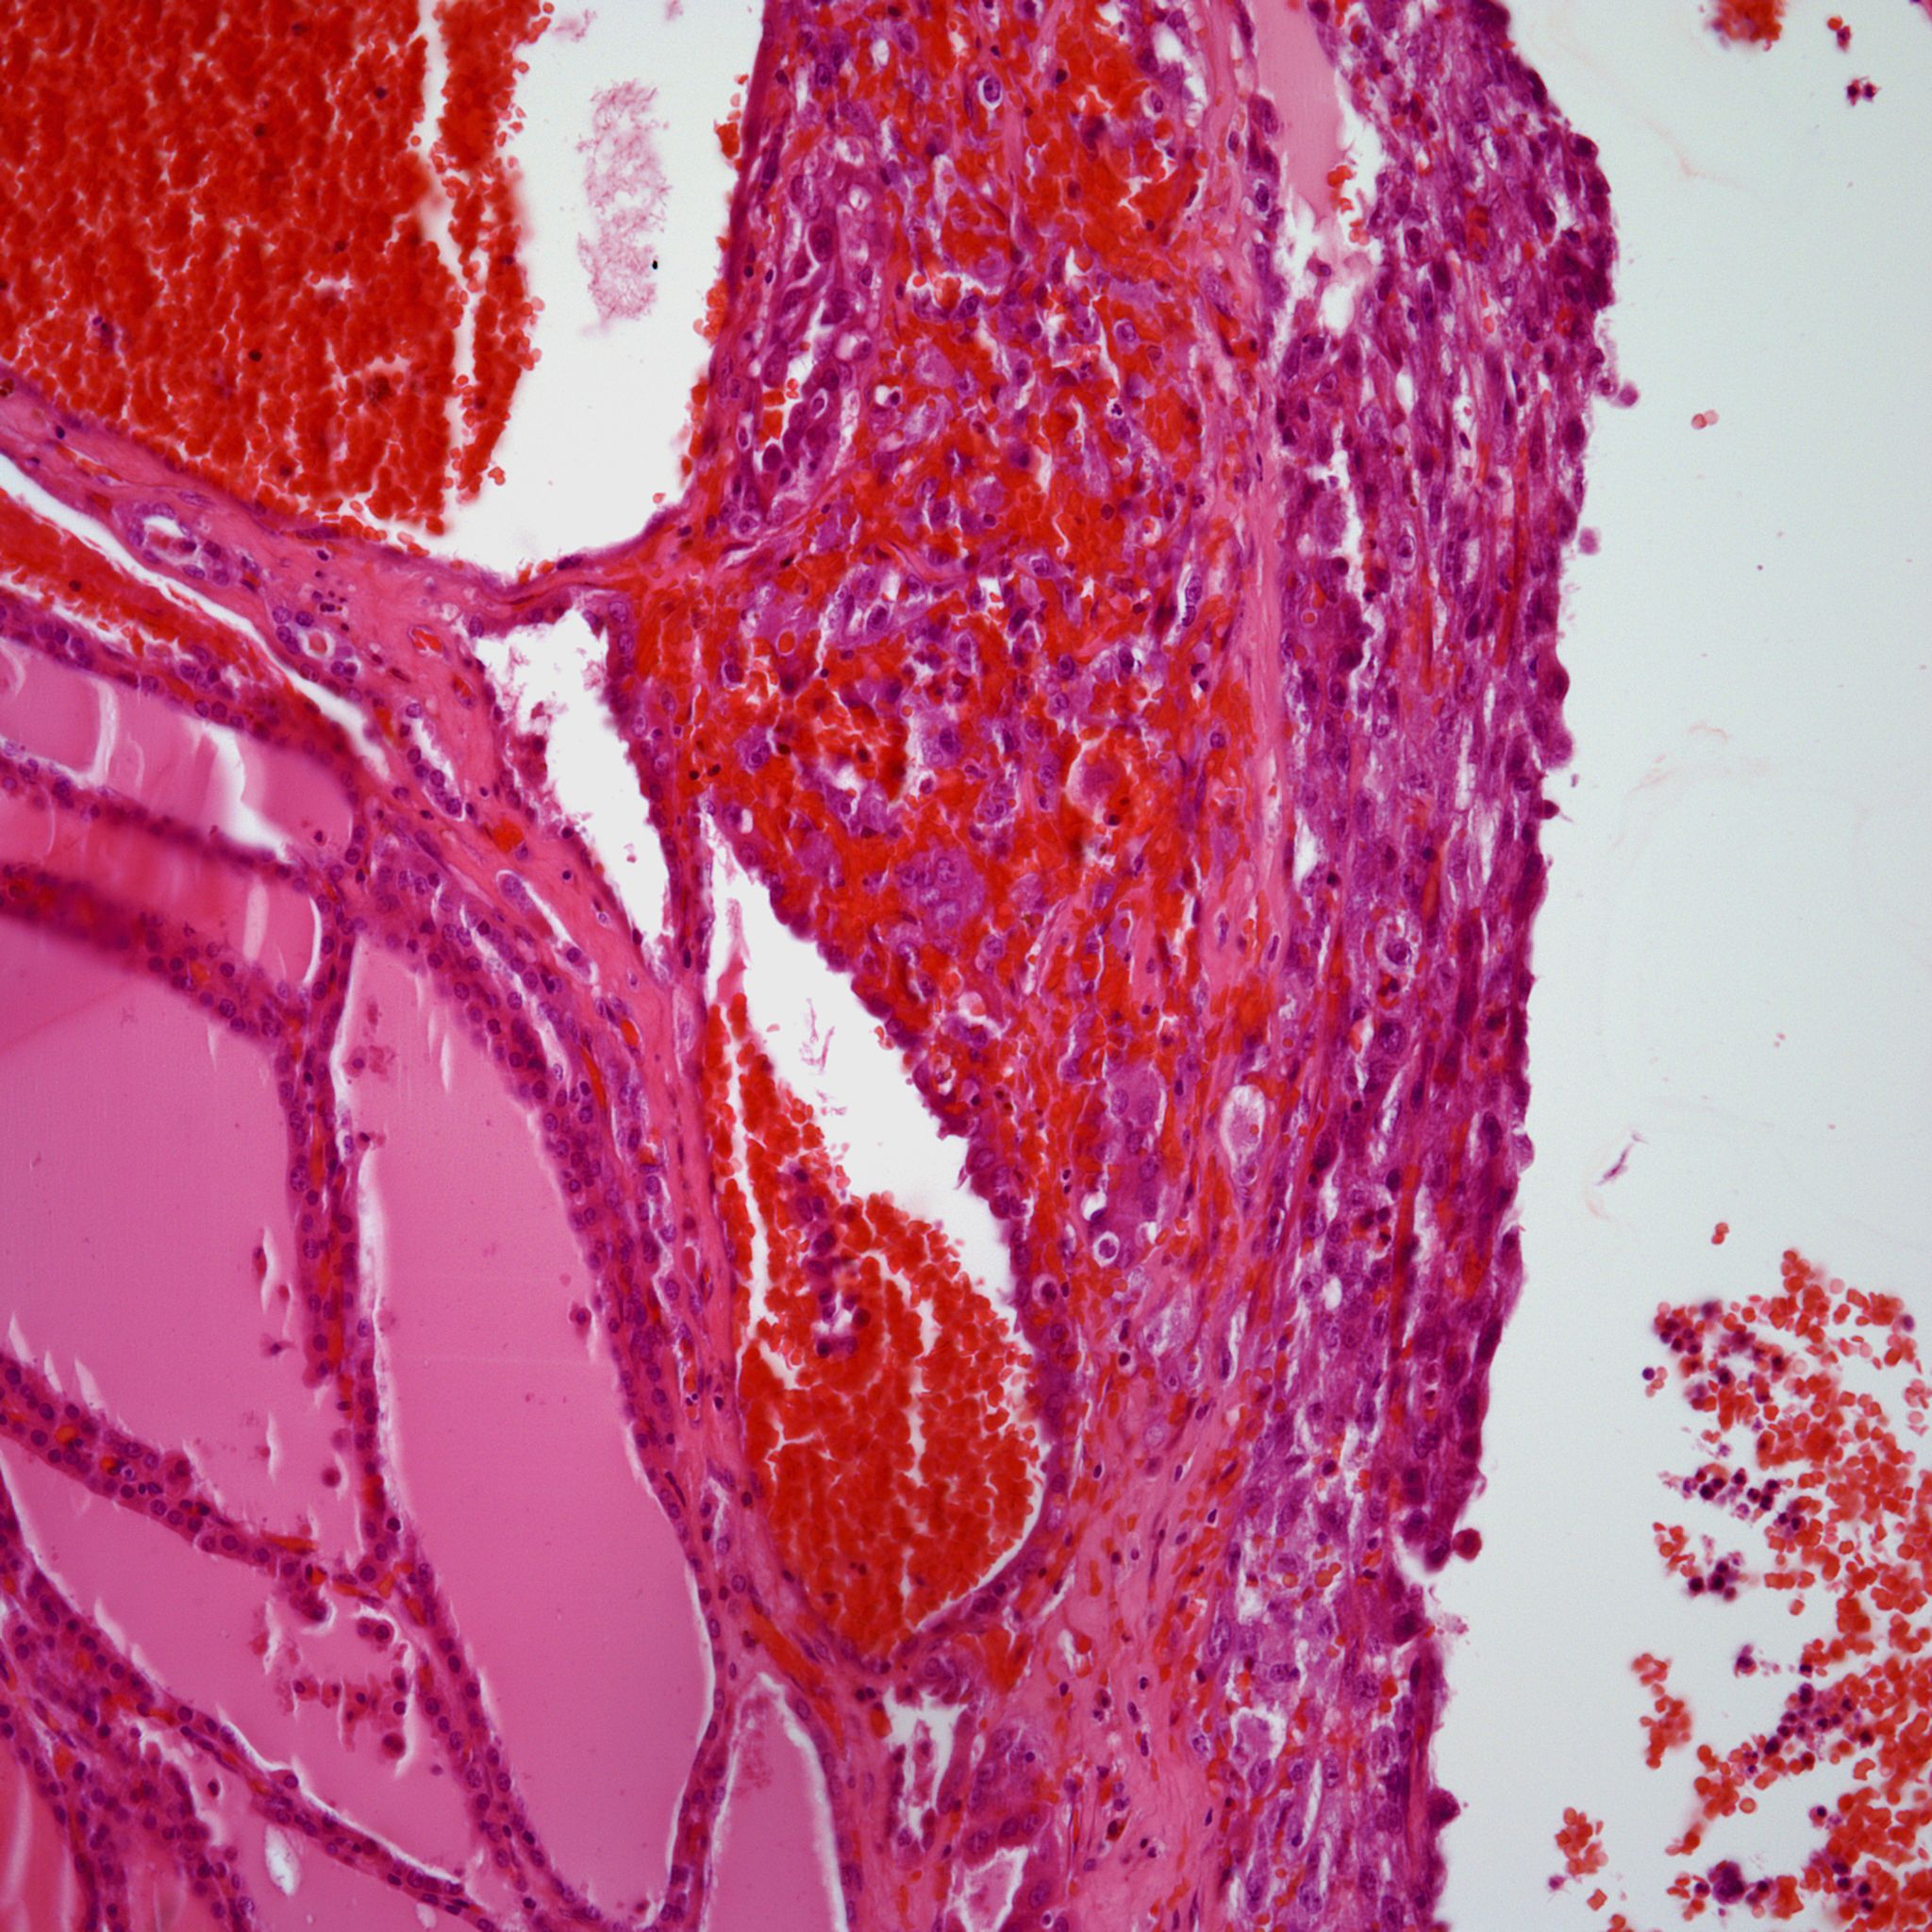

A 73-year-old man presents with neck pain and a mass of possible thyroid origin. What is your diagnosis?

A 73-year-old man presents with neck pain. Physical examination reveals a mass of possible thyroid origin.

Based on the image shown, what is your diagnosis?